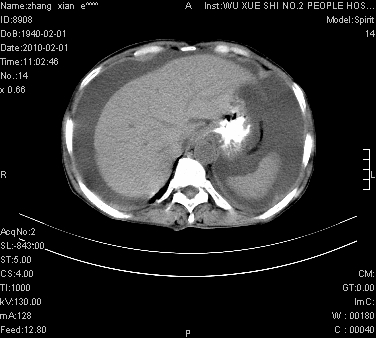

标题: CT24434:70岁 女 腹胀,腹水原因待查 [打印本页]

标题: CT24434:70岁 女 腹胀,腹水原因待查

大量腹水,脾脏囊性占位,子宫颈占位,右侧腹股沟淋巴结肿大,建议+c,先查妇科。

腹盆腔大量积液,子宫增大,子宫颈增大外形不规则,内见低密度影,膀胱后壁显示不清,右腹股沟肿大淋巴结,脾脏囊性占位,子宫颈占位,子宫颈癌?建议增强。

考虑子宫癌并腹水 脾囊肿

子宫、宫颈占位?转移性腹水?肝性腹水?脾脏囊性占位,囊肿?血管瘤?淋巴瘤?